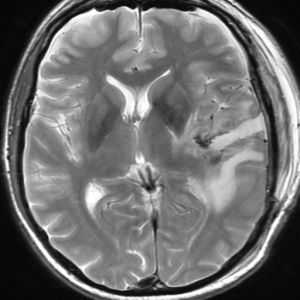

Сообщающаяся (открытая) гидроцефалия после внутримозгового кровоизлияния при разрыве аневризмы

В результате разрыва аневризмы мозговой артерии у больных может формироваться Сообщающаяся (открытая) гидроцефалия. Этот вид гидроцефалии может возникнуть в течение первых 3-х недель после внутримозгового кровоизлияния.

Для диагностики сообщающаяся гидроцефалии после внутримозгового кровоизлияния у пациента используют магниторезонансную (МРТ) или компьютерную томографию (КТ) головного мозга. Сообщающаяся (открытая) гидроцефалия сопровождается расширением боковых, III и IV желудочков головного мозга. Предугадать разовьётся ли у пациента Сообщающаяся (открытая) гидроцефалия после внутримозгового кровоизлияния из-за разрыва аневризмы и насколько она будет выражена невозможно. Скопление значительного количества излившейся крови в субарахноидальном пространстве в области обводной и супраселлярной цистерн может быть признаком формирования у данного больного в дальнейшем сообщающейся гидроцефалии.